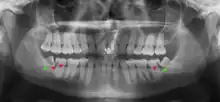

Panoramic radiograph of impacted lower wisdom teeth (green arrows) in a 26-year-old with dental caries (red arrows) on the adjacent teeth

The diagnosis of impaction can be made clinically if enough of the wisdom tooth is visible to determine its angulation, depth, and if the patient is old enough that further eruption or uprighting is unlikely. Wisdom teeth continue to move to the age of 25 years old due to eruption, and then continue some later movement owing to periodontal disease.[18]

If the tooth cannot be assessed with clinical exam alone, the diagnosis is made using either a panoramic radiograph or cone-beam CT. Where unerupted wisdom teeth still have eruption potential several predictors are used to determine the chance of the teeth becoming impacted. The ratio of space between the tooth crown length and the amount of space available, the angle of the teeth compared to the other teeth are the two most commonly used predictors, with the space ratio being the most accurate. Despite the capacity for movement into early adulthood, the likelihood that the tooth will become impacted can be predicted when the ratio of space available to the length of the crown of the tooth is under 1.[5]:141